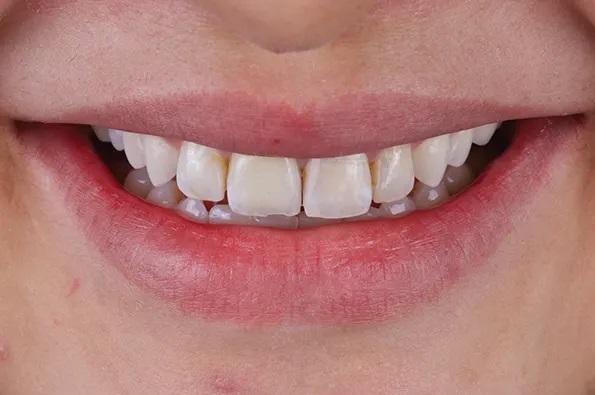

После примерки внутренние поверхности реставраций были протравлены плавиковой кислотой в течение 20 секунд и силанированы в соответствии с инструкциями производителя, а поверхности опор из диоксида циркония были обработаны воздушно-дисперсионной обработкой и специальной керамической грунтовкой в соответствии с APC (воздушно-абразивная обработка, грунтовка с MDP, цемент из композитной смолы) технология склеивания с диоксидом циркония. Была выполнена адгезионная цементировка по протоколу фиксации на полимерный цемент двойного отверждения, стойкого к изменению цвета и имеющего четкий оттенок (Фото 14 – Фото 18).

Фото 15. Улыбка пациентки после лечения вид спереди.